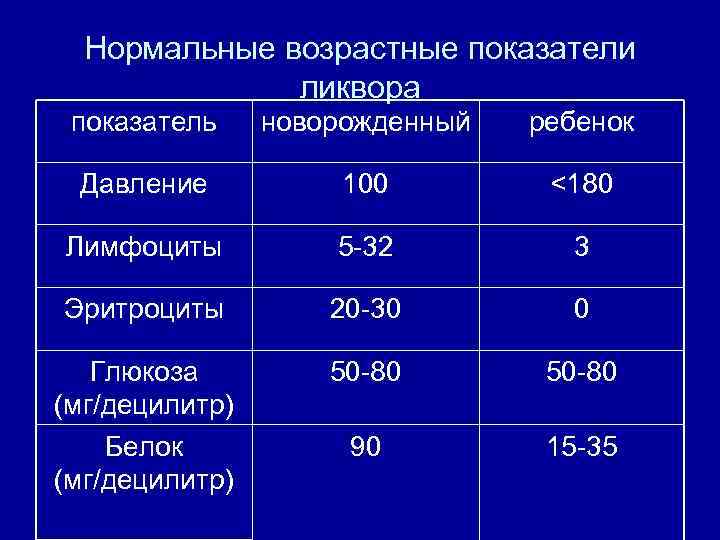

Нормальные возрастные показатели ликвора показатель новорожденный ребенок Давление 100 <180 Лимфоциты 5 -32 3 Эритроциты 20 -30 0 Глюкоза (мг/децилитр) Белок (мг/децилитр) 50 -80 90 15 -35

Нормальные возрастные показатели ликвора показатель новорожденный ребенок Давление 100 <180 Лимфоциты 5 -32 3 Эритроциты 20 -30 0 Глюкоза (мг/децилитр) Белок (мг/децилитр) 50 -80 90 15 -35